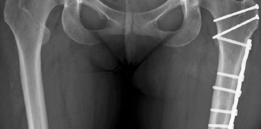

If the patient requires a derotational femoral osteotomy to correct the 36° anteversion, it is performed at this stage. A subtrochanteric osteotomy is executed, the femur is externally rotated to achieve a normalized anteversion of approximately 15°, and rigid fixation is achieved using a pre-contoured locking plate or a blade plate. Following the intra-articular and femoral work, the hip is reduced. The capsule is meticulously closed; a watertight closure is essential to prevent post-operative macro-instability and restore the proprioceptive function of the capsule. Finally, the greater trochanter is reduced and fixed using two or three fully threaded 4.5 mm cortical screws directed medially and slightly proximally toward the lesser trochanter.

Trochanteric non-union or delayed union is a more common complication, occurring in 1% to 3% of cases. It is often related to inadequate fixation, poor bone quality, or premature active abduction during the rehabilitation phase. Patients present with persistent lateral hip pain, a profound abductor lurch, and weakness. Management involves revision internal fixation, often augmented with bone grafting and tension band wiring. Heterotopic ossification (HO) occurs in up to 10% of patients, though clinically significant, motion-limiting HO (Brooker Class III or IV) is rare. Routine prophylaxis with non-steroidal anti-inflammatory drugs (e.g., Indomethacin or Celecoxib for 3-4 weeks post-operatively) is mandatory.